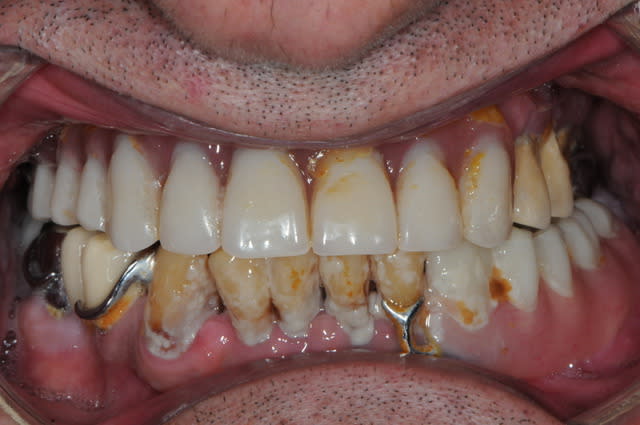

Patient vu en début d'année, parodontite en phase terminale, "monsieur je pense qu'il faudrait vous enlever quelques dents" (voir pano). Lui pas trop pressé apparemment.

Il revient me voir ce mois-ci pour faire sa prothèse. Je lui dit qu'il faut extraire ses dents d'abord.

Il me répond : "ah ben non, elles sont déjà tombées, mais je les garde en bouche ... en attendant!"

Et donc à chaque étape, empreinte, RIM, essayage, je demandais à monsieur d'enlever ses dents, qu'il remettait en place à la fin de la séance.

Du jamais vu pour moi, même si je suis encore jeune dans le métier!!

Fallait que je fasse partager!